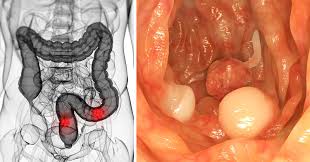

How Do Guys Get Colon Cancer : Colon Cancer Youtube - For this reason, step number two, explains how to reduce your dependence on fiber without experiencing.. Most colon cancers begin as benign polyps. Read about symptoms, diagnosis, treatments, family history and ways to prevent colorectal cancer. Of getting this type of. Colon cancer is the third most common cancer in men and women in the u.s. Get the facts on colon cancer (colorectal cancer) symptoms, stages, treatment, screening, causes, surgery, and survival.

Colorectal cancer almost always develops from precancerous polyps (abnormal growths) in the colon or rectum. Throughout our lives, the lining of the bowel constantly renews itself. How old can you be to have colon cancer&rdquo For example, carcinoembryonic antigen (cea) is a tumor marker for colon cancer. Colon cancer is cancer of the large intestine (colon), which is the final part of your digestive tract.

A family history of polyps or of colon cancer may increase your chances of getting. Colon cancer doctor discussion guide. Some polyps have a stalk and others do not. Colon cancer is cancer of the large intestine (colon), which is the final part of your digestive tract. How does the doctor know i have colorectal cancer? How common is colon cancer? Colon cancer is the third most common cancer. Don't hesitate to get multiple opinions for your treatment; It can affect people of all racial and ethnic groups. Many symptoms can indicate colon cancer in men, including bowel changes, weight loss, cramps, and bloody stool. It usually begins as small get the latest colon cancer help and advice from mayo clinic delivered in your inbox. Its side effects range from severe diarrhea to colon obstruction. Bowel cancer is a cancer that starts in the large bowel and the back passage.

Colon Cancer Symptoms And Causes Mayo Clinic from www.mayoclinic.org The problem is that it will not detect precancerous lesions. Studies have shown that this type of test detects cancer with 92 percent accuracy. My name is adalis martinez and i'm 23 years old. You get colon cancer when a polyp in your large intestine turns into cancer. With colon cancer on the rise in younger men, we talked to experts to help you understand what causes it, when to get a colonoscopy, who is most at that's why medical experts say guys need to start talking about colon cancer now. One defining feature of cancer is the rapid creation of abnormal cells that grow beyond their usual boundaries, and which can then invade adjoining parts of. This factsheet is about bowel (colon) cancer. Some colon cancer cells make markers that travel to the bloodstream.